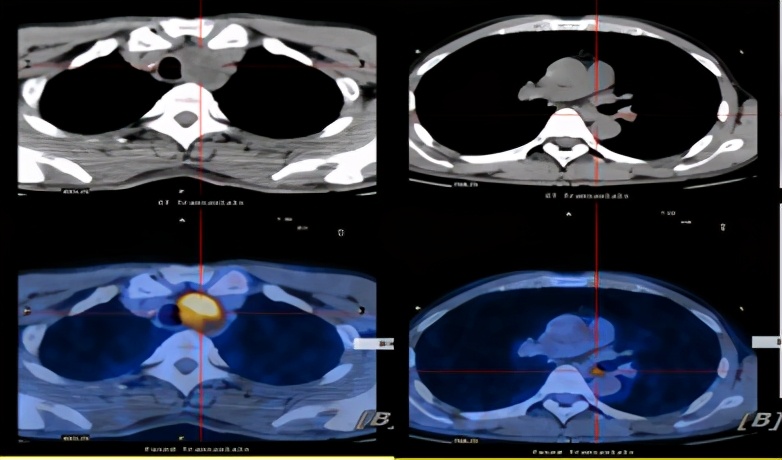

PETCT示:气管左缘软组织密度肿块,与邻近气管左侧壁及食道壁关系密切、分界不清,呈高代谢,考虑恶性肿瘤(淋巴结肿瘤转移可能性大);食道中段管壁局限性略厚,代谢略高,考虑食道癌可能。

治疗前PET/CT